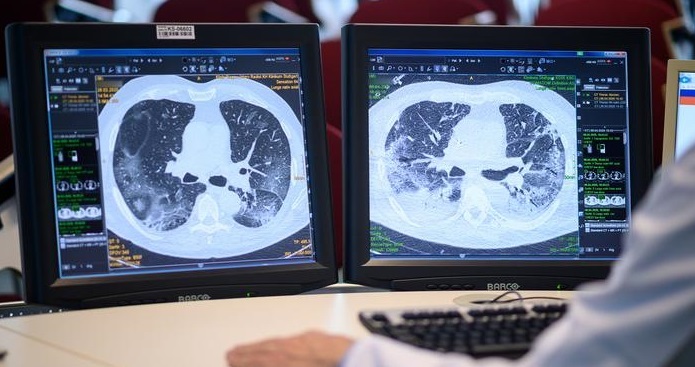

مسیری طولانی برای اسکن ریه در ماهشهر/ فیلم

تردد ۴۰ کیلومتری بیماران مبتلا به کرونا برای سی‌تی‌اسکن ریه در ماهشهر را در این ویدئو ببینید.